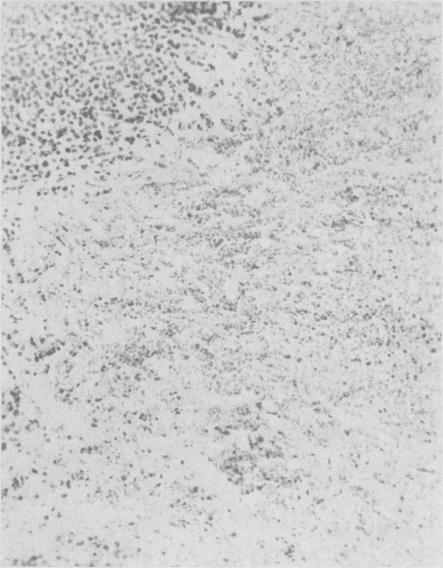

Vincaleukoblastine in the treatment of malignant disease.

Can Med Assoc J. 1961 Sep 2;85(10):584-91.